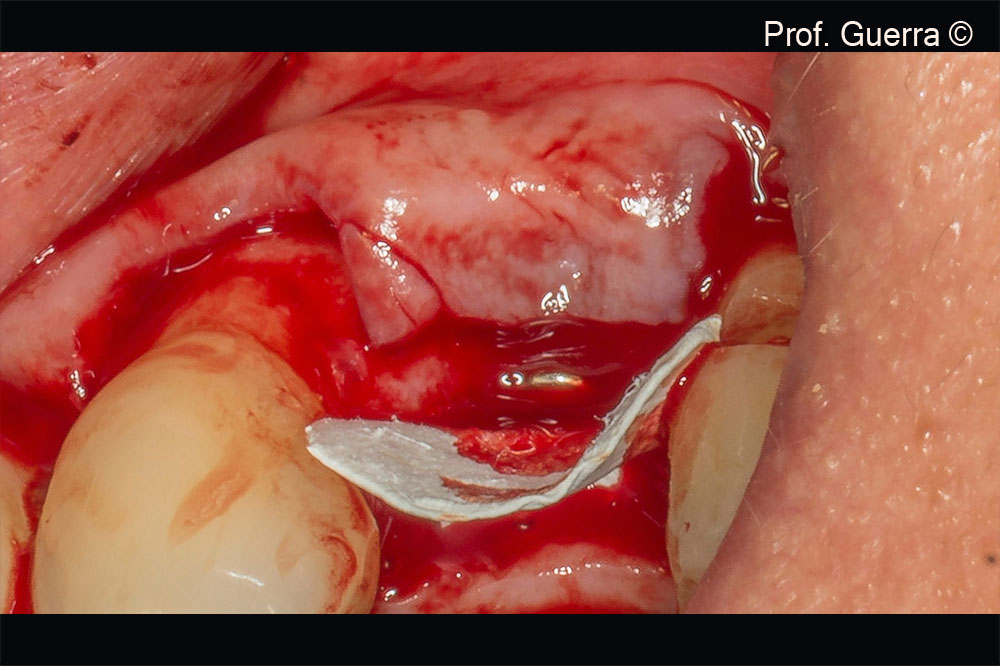

Left) two-stage implant surgery; Right) membrane trimming